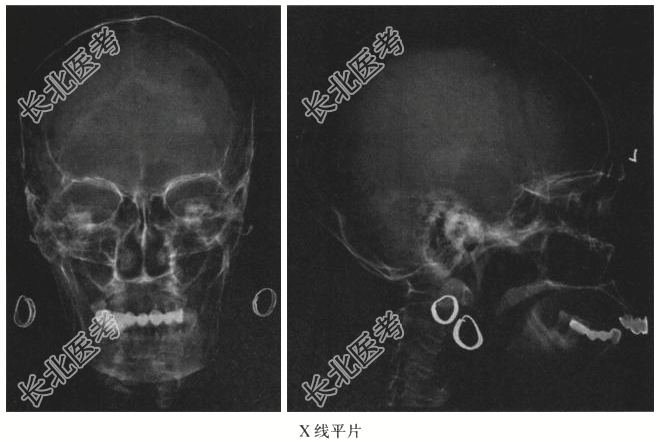

- [材料题] 患者女,76岁,食欲缺乏、乏力伴全身多处疼痛3周入院,无肿瘤病史,行头颅X线平片如图所示。

- 简答题1、根据病史及影像资料,首先考虑为?